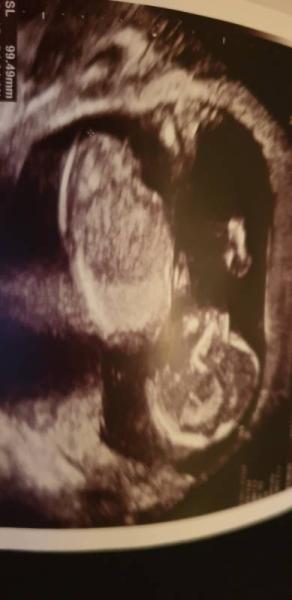

...sooo...nun war heute der "lang" ersehnte Termin nach dem ETS. Da gab es ja schon die Tendenz Team Rosa. Aber ich hatte Angst das es nicht stimmt. Auch heute hat sie zwischen den Beinchen geschaut.. Aber zu erst hat sie meinem Mann alles gezeigt - er war heute das erste mal dabei. Es hat sogar Greifübungen gemacht..so süß. Es ist 10cm von Kopf bis Po, also insgesamt ca 15cm meinte sie..alles super und in Ordnung. Laut US wiegt es schon 125g !!! Sie bleibt dabei, es sieht verdächtig nach Team Rosa aus..zwischen den Beinchen ist nichts..da hing kein Zipfel...sie hat auch währens des Ultaschalls immer gesagt "sie winkt, sie hat einen schönen kopf" etc. Das würde sie ja hoffentlich nicht sagen wenn sie sich nicht sicher wäre. Wie gesagt..der große war bei 12+ auch n mädel und bei 15+ hat sie dann doch junge gesagt.. Diesmal meinte sie bei 13 schon Mädchen und heute bei 15+ auch..ich hoffe so das es stimmt..habe mir sogar ein Tränchen verdrückt. Gern würde ich ein Rosa Kleidchen kaufen..aber ob ich jetzt nochmal 4wochen warten sollte dafür?? Ganz zu Beginn des Schalls war sie von der Seite zu sehen und der NUB war auch (meiner Meinung nach) total Mädchen. Meint ihr ich kann ihr glauben und wenigstens 2 rosa teile kaufen?:(

Bild zu Zurück vom Baby-TV mit Outing - Forum für April - Mamis